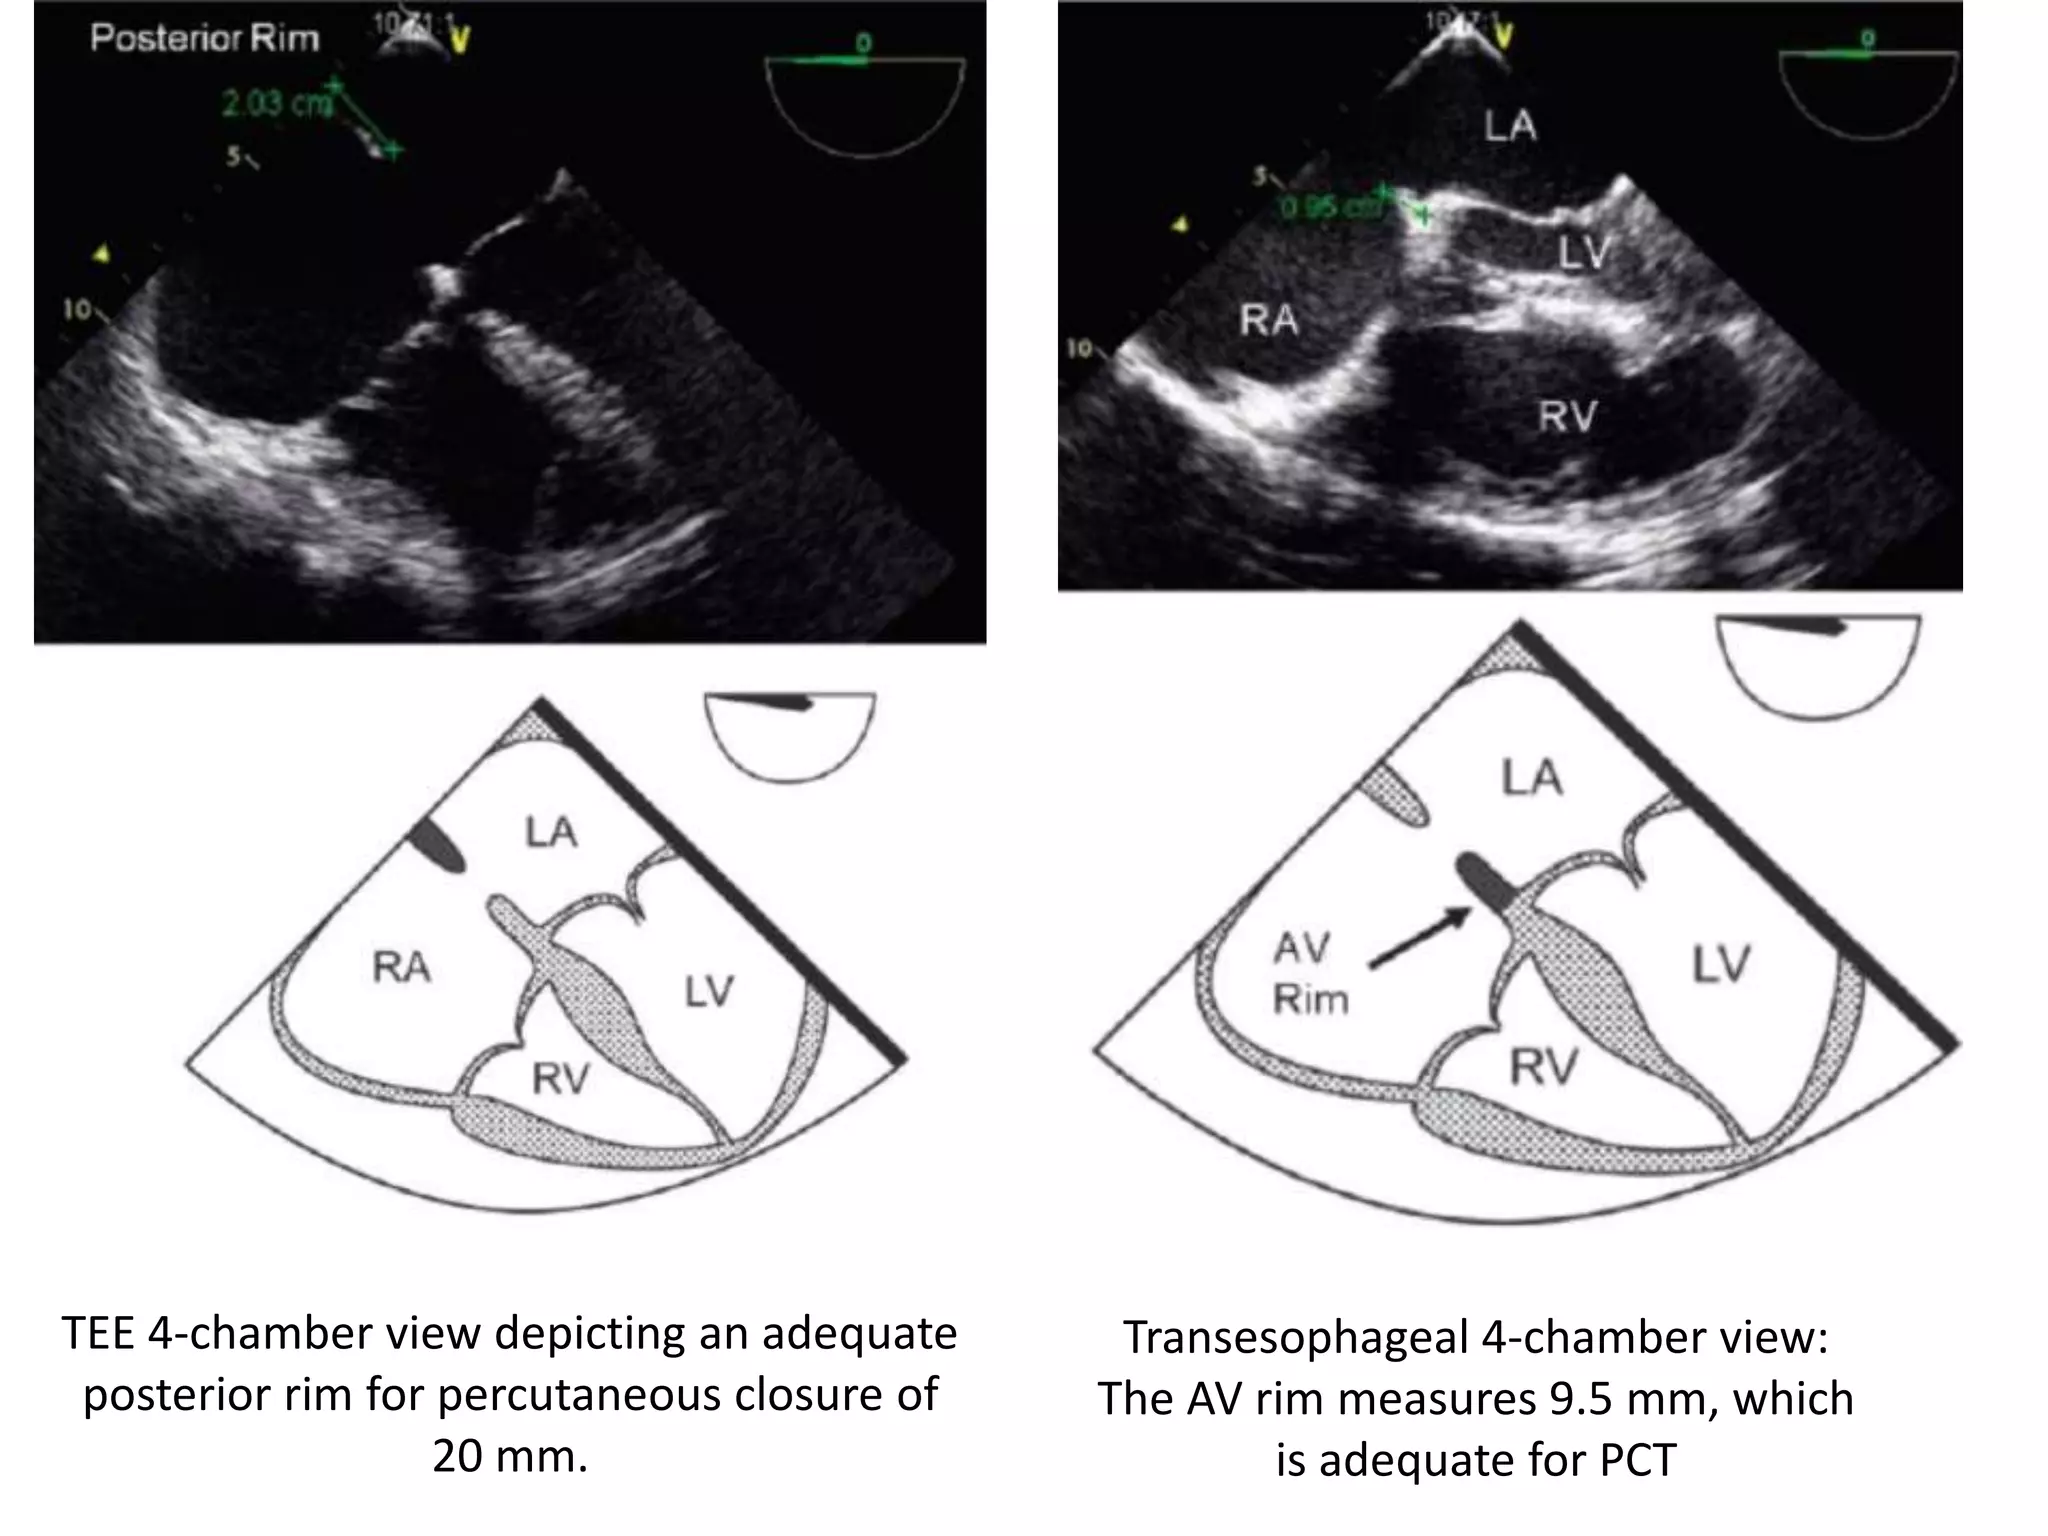

TEE 4-chamber view depicting an adequate

posterior rim for percutaneous closure of

20 mm.

Transesophageal 4-chamber view:

The AV rim measures 9.5 mm, which

is adequate for PCT

TEE 4-chamber viewdepicting an adequate posterior rim for percutaneous closure of 20 mm. Transesophageal 4-chamber view: The AV rim measures 9.5 mm, which is adequate for PCT